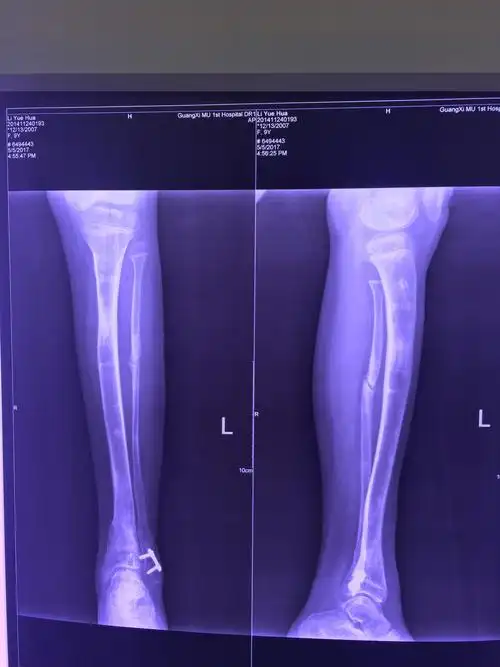

小腿短缩,踝内翻畸形,行重建和延长 - 好大夫在线